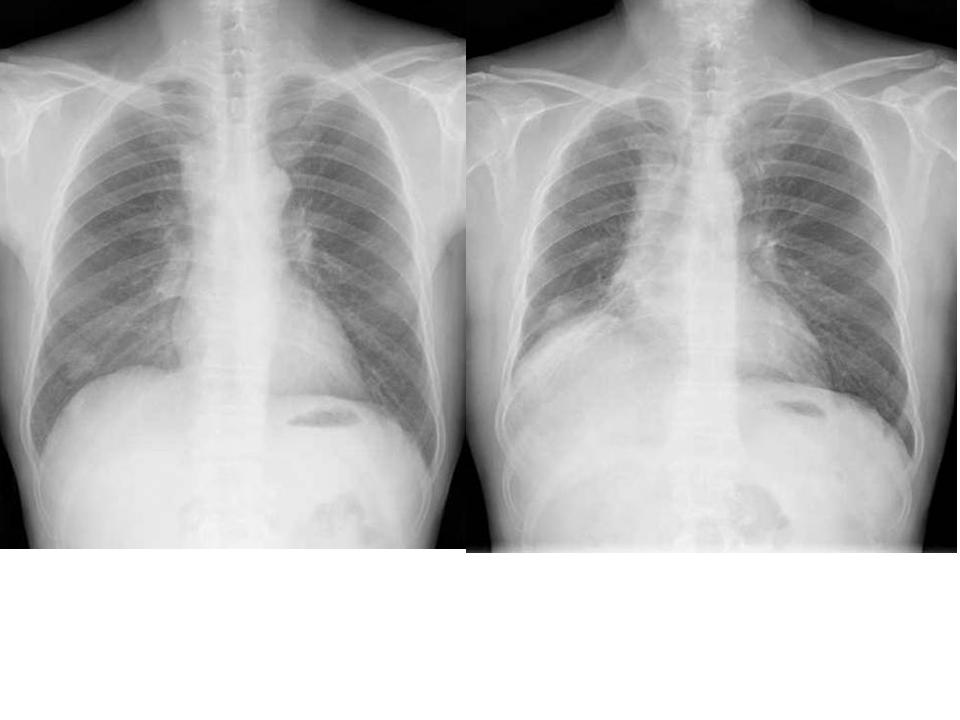

Aシルエット・サインを使う

陰影があったときに、果たしてその陰影はどこにあるのか。

上、中、下肺野のどこにあるかとともに、シルエット・サインをうまく使うことでどのセグメント(

1〜10に分かれている、例のやつ)を絞り込むことができます。